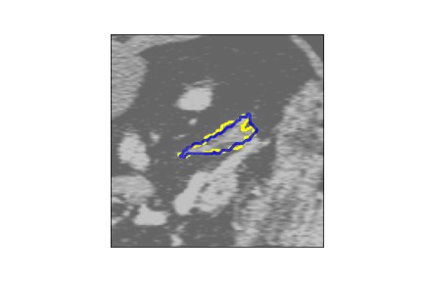

The human annotations are imperfect, especially when produced by junior practitioners. Multi-expert consensus is usually regarded as golden standard, while this annotation protocol is too expensive to implement in many real-world projects. In this study, we propose a method to refine human annotation, named Neural Annotation Refinement (NeAR). It is based on a learnable implicit function, which decodes a latent vector into represented shape. By integrating the appearance as an input of implicit functions, the appearance-aware NeAR fixes the annotation artefacts. Our method is demonstrated on the application of adrenal gland analysis. We first show that the NeAR can repair distorted golden standards on a public adrenal gland segmentation dataset. Besides, we develop a new Adrenal gLand ANalysis (ALAN) dataset with the proposed NeAR, where each case consists of a 3D shape of adrenal gland and its diagnosis label (normal vs. abnormal) assigned by experts. We show that models trained on the shapes repaired by the NeAR can diagnose adrenal glands better than the original ones. The ALAN dataset will be open-source, with 1,594 shapes for adrenal gland diagnosis, which serves as a new benchmark for medical shape analysis. Code and dataset are available at https://github.com/M3DV/NeAR.